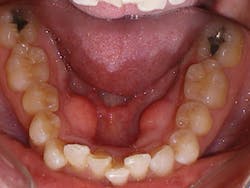

Sandra is a common example of a patient having a malocclusion that is the direct cause of her recession, and abfractions. When we first examined Sandra, her chief complaint was her smile (see Figure 3). She was unhappy with her smile and "crooked" teeth and had the desire to fix them.

At the consultation, Sandra's photos were used to teach. The photo of the lower crowding with the lingual plaque and calculus was used to teach Sandra the difference between crowded teeth and aligned teeth. We also informed her that her teeth are not actually "crooked" (her chief complaint). The mandibular occlusal view pointed out her V-shaped arch provided no room for her teeth to fit within the arch.

The remaining photos were used to teach the difference between a good bite and a bad bite. Sandra learned about clefting, recession, abfractions, and the visible areas of enamel wear on multiple teeth. Sandra understood that clear aligner therapy would change her bad bite to a good bite, resulting in a beautiful, healthy smile. My goal went further than that. I knew the benefits of aligned teeth include increased longevity, a healthy periodontium, and proper occlusion for her to enjoy a lifetime of oral health.